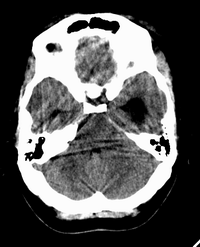

患者,女性,33岁,外伤检查发现,既往没有明显类似病史。

ct平扫见左侧脑室后角不规则形,边界不清的等密度肿块,肿瘤内有钙化,瘤周可见残存的脑室(低密度脑脊液影),考虑脉络脉丛乳头状瘤或室管膜瘤.

左侧侧脑室三角区占位性病变,其特点是平扫边界清、密度高、其内可见大块结节样的钙化,首先考虑起源于侧脑室三角区残余蛛网膜上皮的脑膜瘤可能性最大,无论是形态、密度、好发部位均符合脑膜瘤特点,建议增强进一步检查。

左侧脑室内软组织肿物,内部见多发不规则钙化,边界清楚锐利,有分叶。相应左侧脑室扩张。常见的不外乎3种病:室管膜瘤,脑膜瘤,脉络脉丛乳头状瘤。脑膜瘤分叶较少见,脉络脉丛乳头状瘤钙化较少见,因此,室管膜瘤可能性最大。

左侧脑室内见不规则略高密度团块影,边缘分叶,内见多发不规则钙化,病灶与侧脑室壁关系较为密切,左侧脑室扩大。考虑室管膜瘤可能性较大,其次为脑膜瘤,脉络丛乳头状瘤的可能性最小。

平扫见左侧脑室三角区不规则形肿块,肿瘤内有钙化,瘤周可见残存的脑室(低密度脑脊液影),考虑脉络脉丛乳头状瘤或室管膜瘤.